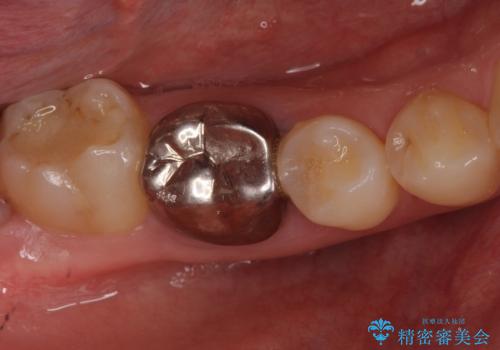

- 右下の奥歯に入れた銀歯を白くしたいとのことで来院されました。

根っこの治療がされていますが、症状もなくレントゲン画像で病変も確認できないため根管内には触れず被せ物のやり替えのみとなりました。

下の奥歯は口を開くと簡単に外から見えてしまいます。